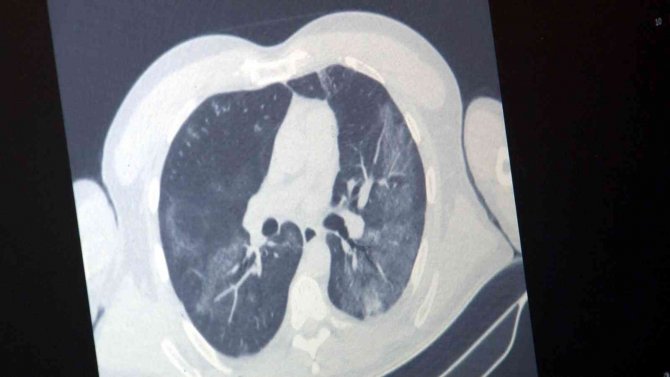

"Bu virüsün yıllardır uyguladığımız kendi aşısı var ama influenza vakalarını çok görmediğimiz için bu sene aşı sayısı oldukça azaldı. Bununda etkisiyle influenza vakalarımız epey artmış durumda. Domuz gribi influenzanın bir tipidir. Kuş gribi de influenzanın bir tipidir. Bu virüslerin genel ismi influenza virüsüdür. Korona virüste, influenza da solunum yoluyla bulaşır. Klinik durumda ayırt etmek oldukça zordur. Her ikisi de akciğer tutulumu ve ateş yapabilir. İnfluenza da eklem ağrılarını biraz daha fazla görüyoruz. Tat ve koku kaybı influenza da çok beklediğimiz bir durum değil. İnfluenza özellikle gebelerde, 65 yaş üstünde, KOAH'ı ve diyabeti olan hastalarda daha ağır seyreder. Buna dikkat etmek gerekir. Vatandaşlarımız maske kullanmaya dikkat etsinler. Kapalı ve kalabalık ortamlardan mümkünse uzak dursunlar. El hijyeninin önemi de halen devam ediyor."